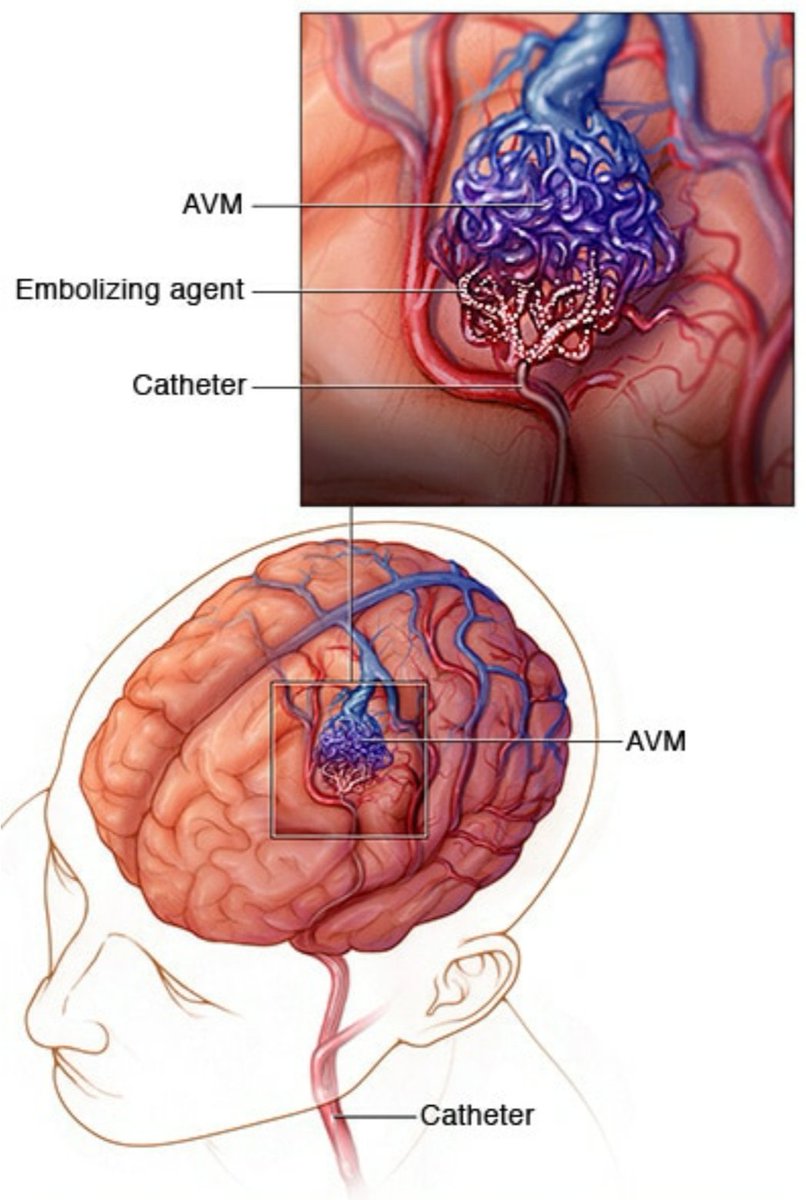

🧠اشعه بالصبغه

🧠اشعه تداخليه بالقسطرة للتشخيص والعلاج

🧠اشعه تداخليه بالقسطرة للتشخيص والعلاج

🧠تشوهات خلقيه في اوعية المخ الدمويه المختلفة

🧠تشوهات خلقيه في اوعية المخ الدمويه المختلفة

♦️قسطرة تداخليه لسحب الجلطه من الشرايين الرئيسيه ان وجدت

♦️قسطرة تداخليه لسحب الجلطه من الشرايين الرئيسيه ان وجدت

🧠عملية القسطرة التي يمكن إجراءها

♦️اول ٦ ساعات♦️من ظهور الأعراض